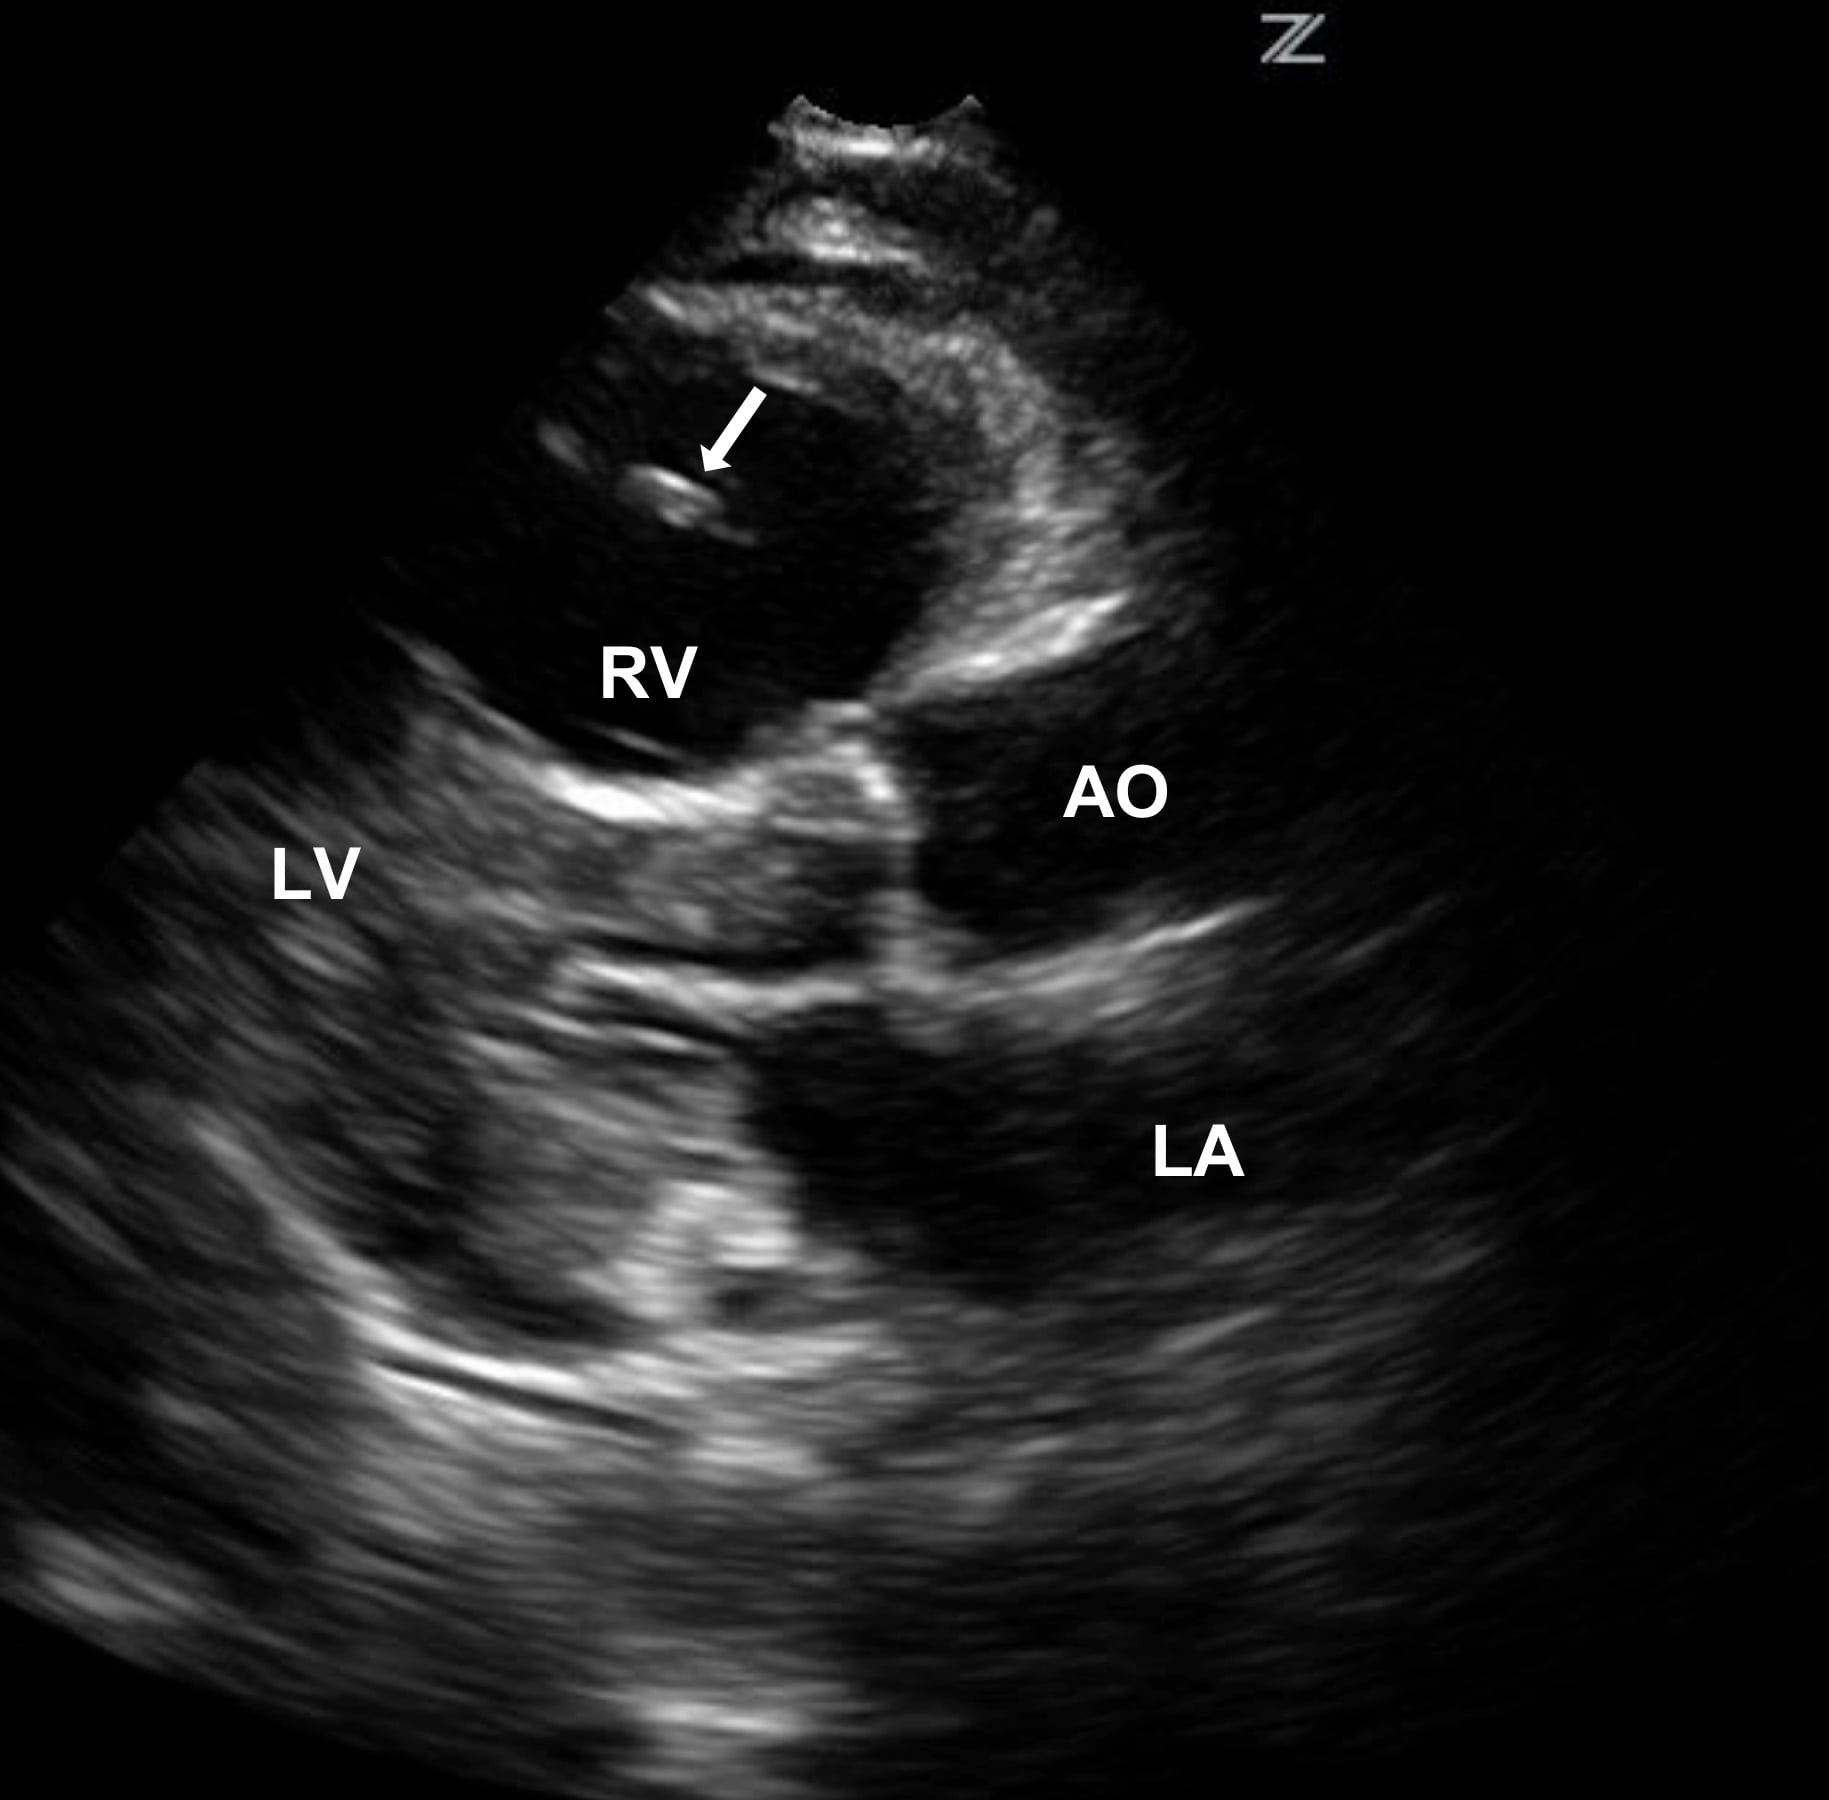

Bedside Echocardiography for Undifferentiated Hypotension Diagnosis of Blood Clot Near Heart Venous thromboembolism occurs in veins or arteries, most commonly in the legs. Coronary thrombosis is a blockage of an artery in the heart, which can lead to a heart attack. When a blood clot travels to the lungs and causes a blockage of an artery, it’s called a pulmonary embolism. If you experience chest pain, labored breathing, or coughing up. Blood Clot Near Heart.